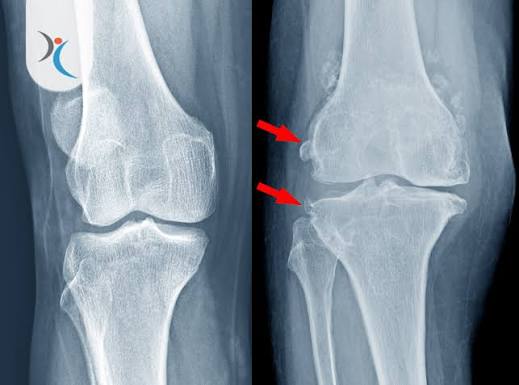

كشفت دراسة علمية حديثة عن آلية واعدة قد تمهّد الطريق لعلاج جذري لخشونة المفاصل، من خلال استهداف بروتين يُعرف باسم 15-PGDH، والذي تبيّن أنه يلعب دورًا محوريًا في تدهور الغضروف مع التقدم في العمر.

البحث، الذي قاده فريق من جامعة ستانفورد، أظهر أن ارتفاع مستويات هذا البروتين يرتبط بضعف قدرة الأنسجة على التجدد وزيادة الالتهاب، وهو ما يساهم في تطور التهاب المفاصل العظمي، أحد أكثر أمراض المفاصل شيوعًا.

في تجارب مخبرية على فئران متقدمة في العمر، أدى تثبيط نشاط البروتين إلى نتائج لافتة، حيث زادت سماكة غضروف الركبة المتآكل، واستعاد جزءًا من خصائصه الطبيعية من حيث المرونة والكثافة. كما أظهرت تجارب على فئران أصغر سنًا أن هذا النهج لا يقتصر على العلاج، بل يمتد ليشمل الوقاية من تطور المرض بعد الإصابات.